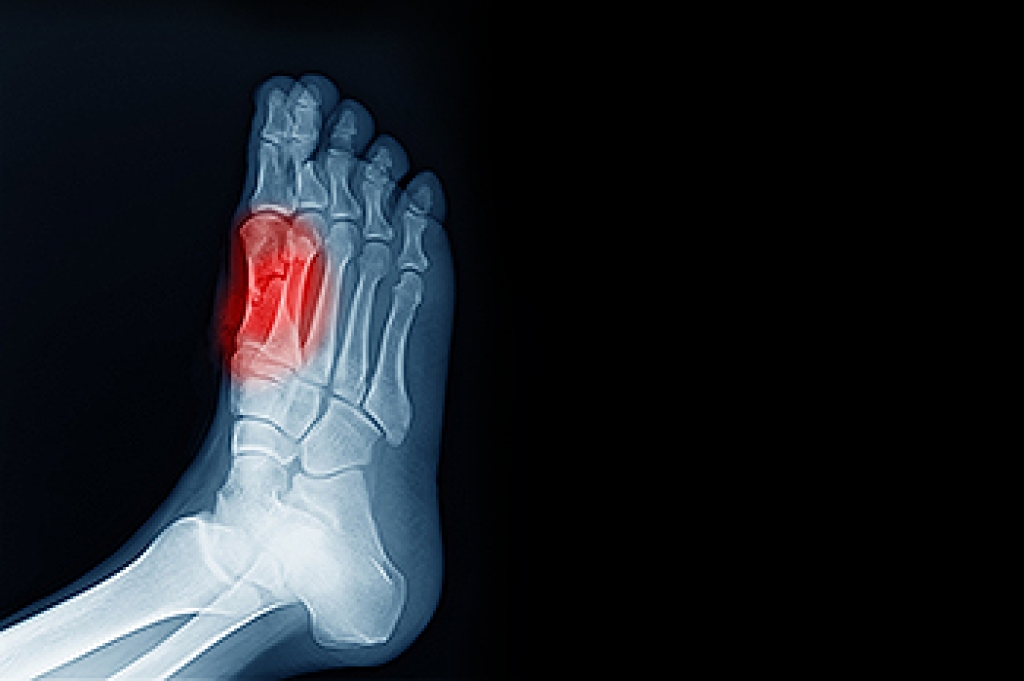

Sesamoiditis refers to inflammation of the sesamoid bones, the two small, pea-shaped bones located beneath the big toe joint within the tendons. These bones help the big toe move smoothly and bear weight during walking and running. Causes of sesamoiditis can include repetitive stress from activities that exert pressure on the forefoot, such as dancing or running, as well as wearing high heels or tight shoes that increase pressure on the ball of the foot. Symptoms include pain under the big toe, which worsens when bearing weight or bending the toe. Diagnosis involves a physical examination to assess tenderness and range of motion, in addition to imaging tests like X-rays to visualize the sesamoid bones and rule out fractures. Relief options include rest, cushioning pads, and footwear modifications. In severe cases, immobilization in a cast or surgical removal of the sesamoid bone may be necessary to alleviate pain and restore function. If you have pain under your big toe, it is suggested that you consult a podiatrist who can provide a diagnosis, and offer you a comprehensive treatment plan.

Sesamoiditis is a condition of the foot that affects the ball of the foot. It is more common in younger people than it is in older people. It can also occur with people who have begun a new exercise program, since their bodies are adjusting to the new physical regimen. Pain may also be caused by the inflammation of tendons surrounding the bones. It is important to seek treatment in its early stages because if you ignore the pain, this condition can lead to more serious problems such as severe irritation and bone fractures.